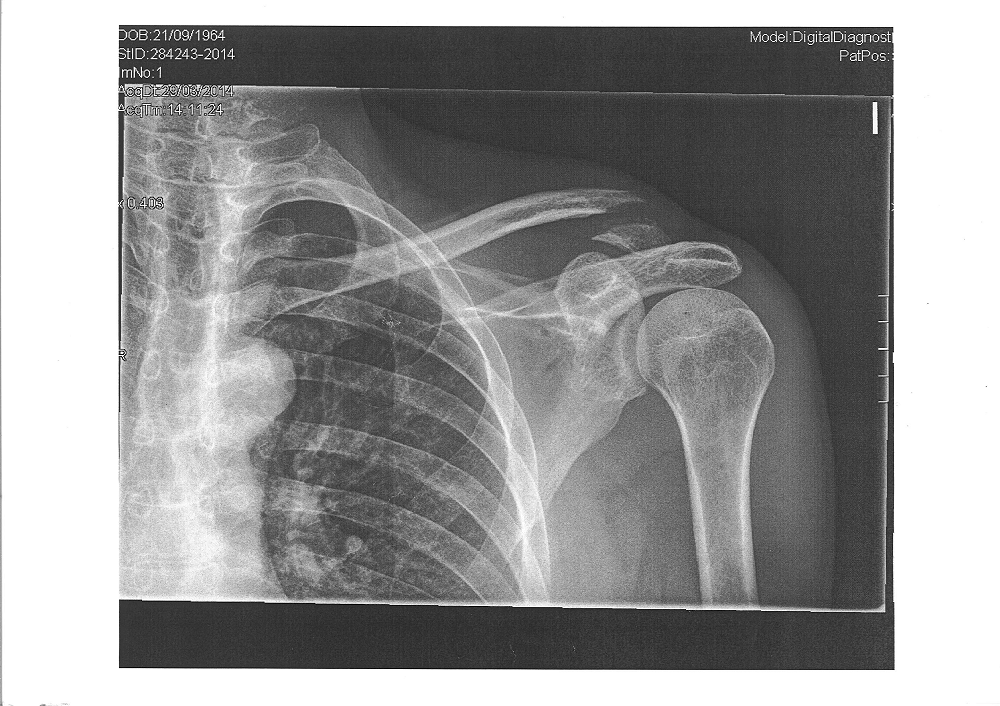

Y como se puede apreciar, me rompí la clavícula. Ahora llevo dos clavos que la sujetan y que presumiblemente favorecerán que suelde adecuadamente. Maravillas de la técnica y de la sanidad pública.

El otoño de 2014, si no surgen imponderables, será una estación mágica para mí. Así lo he decidido, y para ello me voy a preparar, con el apoyo de mi familia y de mis amigos. Asumo el reto con ilusión. Volveré a leer mis manuales de entrenamiento, volveré a diagnosticar periódicamente mi estado de forma física, deberé llevar a cabo una correcta rehabilitación de mi clavícula, cuidar la alimentación, programar las actividades deportivas, comprobar la progresión y sobre todo, compartir el reto con mis amigos y compañeros de entrenamiento.